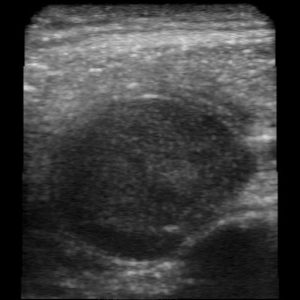

فقد كان يشعر بشعور غير مريح وبضخامة في حنجرته، فقام بوضع بعض الهلام على عنقه وحرَّك عليه الرأس الفاحص للجهاز -الذي له حجم ماكينة الحلاقة الكهربائية وشكلها- فظهرت صور سوداء ورمادية بسرعة على هاتفه الذكي المتصل بالجهاز. إن مارتن ليس اختصاصياً في السرطان، ولكنه كان يعلم بأن الكتلة القاتمة التي لاحظها بطول ثلاثة سنتيمترات لم تكن طبيعية، وهو يقول: "لقد كنت طبيباً بما يكفي لأعرف أنني أواجه مشكلة". وهذه الكتلة كانت عبارة عن سرطان الخلايا الحرشفية.

وكان الجهاز الذي استخدمه يسمَّى بترفلاي آي كيو (Butterfly IQ)، وهو أول جهاز تصوير بالموجات فوق الصوتية بالدارت الإلكترونية يصل إلى الأسواق في الولايات المتحدة. إذ تعمل أجهزة التصوير بالموجات فوق الصوتية عن طريق إصدار صوت إلى الجسم والتقاط الصدى، وعادةً ما يتم توليد الموجات الصوتية بواسطة بلّورات مهتزة، ولكن جهاز بترفلاي يستخدم بدلاً من ذلك 9 آلاف دارة صغيرة مثبّتة على رقاقة نصف ناقلة.

ويقول جون كيندل (مدير التصوير بالموجات فوق الصوتية في قسم الطوارئ في مركز دنفر الصحي الطبي وأحد مستشاري الشركة) إن الصور التي يُنتجها الجهاز ليست بدقة الصور التي تنتجها أجهزة التصوير بالموجات فوق الصوتية المتطوّرة الجوّالة. ولكنه يقول: "إلا أن السؤال هو مدى إمكانية أن أحصل على إجابة تشخيصية أفضل". وذلك بالنظر إلى تكلفة الجهاز والطريقة التي يمكنه بها وضعه في الجيب العلوي لردائه، ويختتم بقوله: "إن المقارنة ليست عادلة حتى، فهو جهاز محمول بشكل مطلق، بل إنه ليس من نفس النوع من الأجهزة".

وتقول الشركة إنها تأمل في الجمع بين الأداة وبرمجيات الذكاء الاصطناعي التي يمكنها أن تساعد المبتدئين في وضع الرأس الفاحص والتقاط الصور الصحيحة وتفسيرها، وتعتقد أنه بحلول العام المقبل فإن برنامجها سيسمح للمستخدمين تلقائياً بحساب كمية الدم التي يضخها القلب، أو الكشف عن بعض المشاكل مثل تمدُّد الأوعية الدموية الأبهري. وتم وصف العمل في هذا الاتجاه في مقطع فيديو أصدرته الشركة.

ويمكن أن يؤدي التفسير التلقائي لصور الموجات فوق الصوتية الضبابية في النهاية إلى تحويل هذه التقنية إلى شيء يسهل استخدامه من قِبل العاملين في سيارات الإسعاف أو في المناطق النائية أو حتى في المنزل. ويقول كيندل: "إن إمكانية الحصول على الصورة ومعرفة ما تراه هي إمكانية قادمة كما أعتقد".